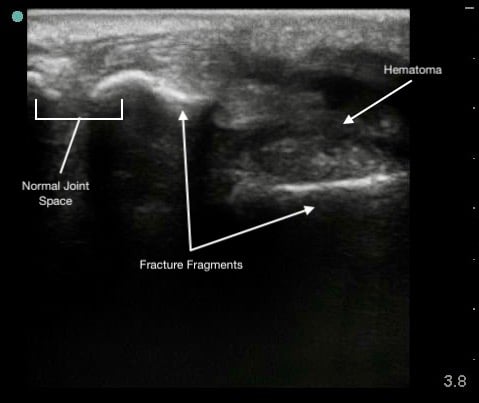

Figure 6.

Colles (distal radius) fracture.

Hypoechoic hematoma or effusion may be visible in the surrounding soft tissue.

Ultrasound allows immediate assessment of the presence and extent of a fracture at the area of tenderness.

Capable of detecting displacement as small as 1 mm.

Less effective for evaluating fracture geometry or comminution.

Ultrasound guidance can enhance the effectiveness of hematoma blocks by ensuring accurate anesthetic delivery.